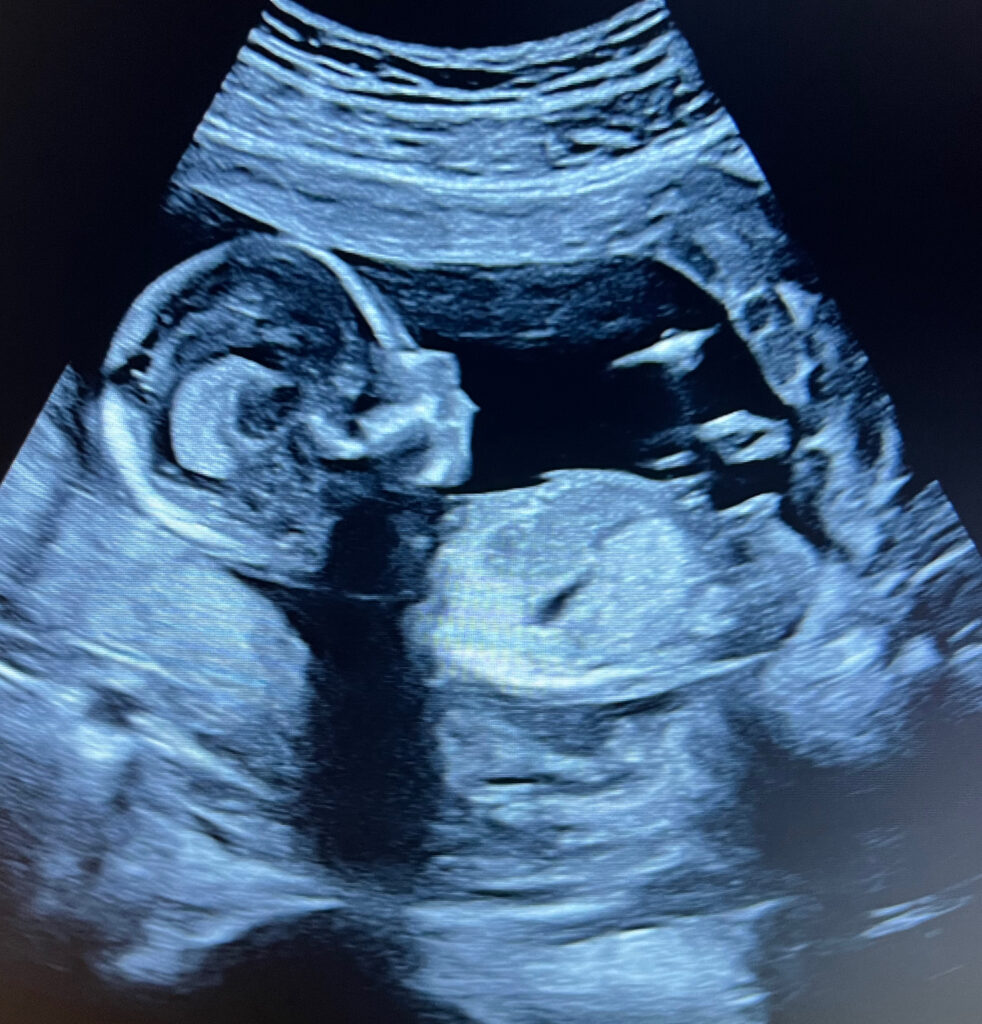

Van de eerste echo omdat je niet kunt wachten tot je bij de verloskundige terecht kunt tot nog even spieken bij 37 weken omdat je de baby al zo lang niet hebt gezien.

Een vroege echo kan worden ingepland vanaf 6 weken zwangerschapsduur. Veel eerder dan dat zou wel kunnen maar geeft je als zwangere niet meer informatie. De hartactie van de baby begint te kloppen bij 5 weken en 4 dagen, maar is heel vaak met de echo pas zichtbaar na 6 weken zwangerschap. Om onzekerheid te voorkomen of de zwangerschap wel of niet goed is zien wij je dus het liefst pas na 6 weken zwangerschapsduur.

Vroege echo

Vanaf 6 weken tot 10 weken 10 min, inclusief 2 zwart/wit foto afdrukken (dit is altijd een echo via de buik) . Dit is de eerte echo na een positieve test en kan al voordat je bij de verloskundige terecht kan gemaakt worden bij ons. We kunnen metingen doen wat betreft het aantal weken en bekijken of er een kloppend hartje te zien is! Je weet dus direct hoe ver je bent en of alles goed zit!